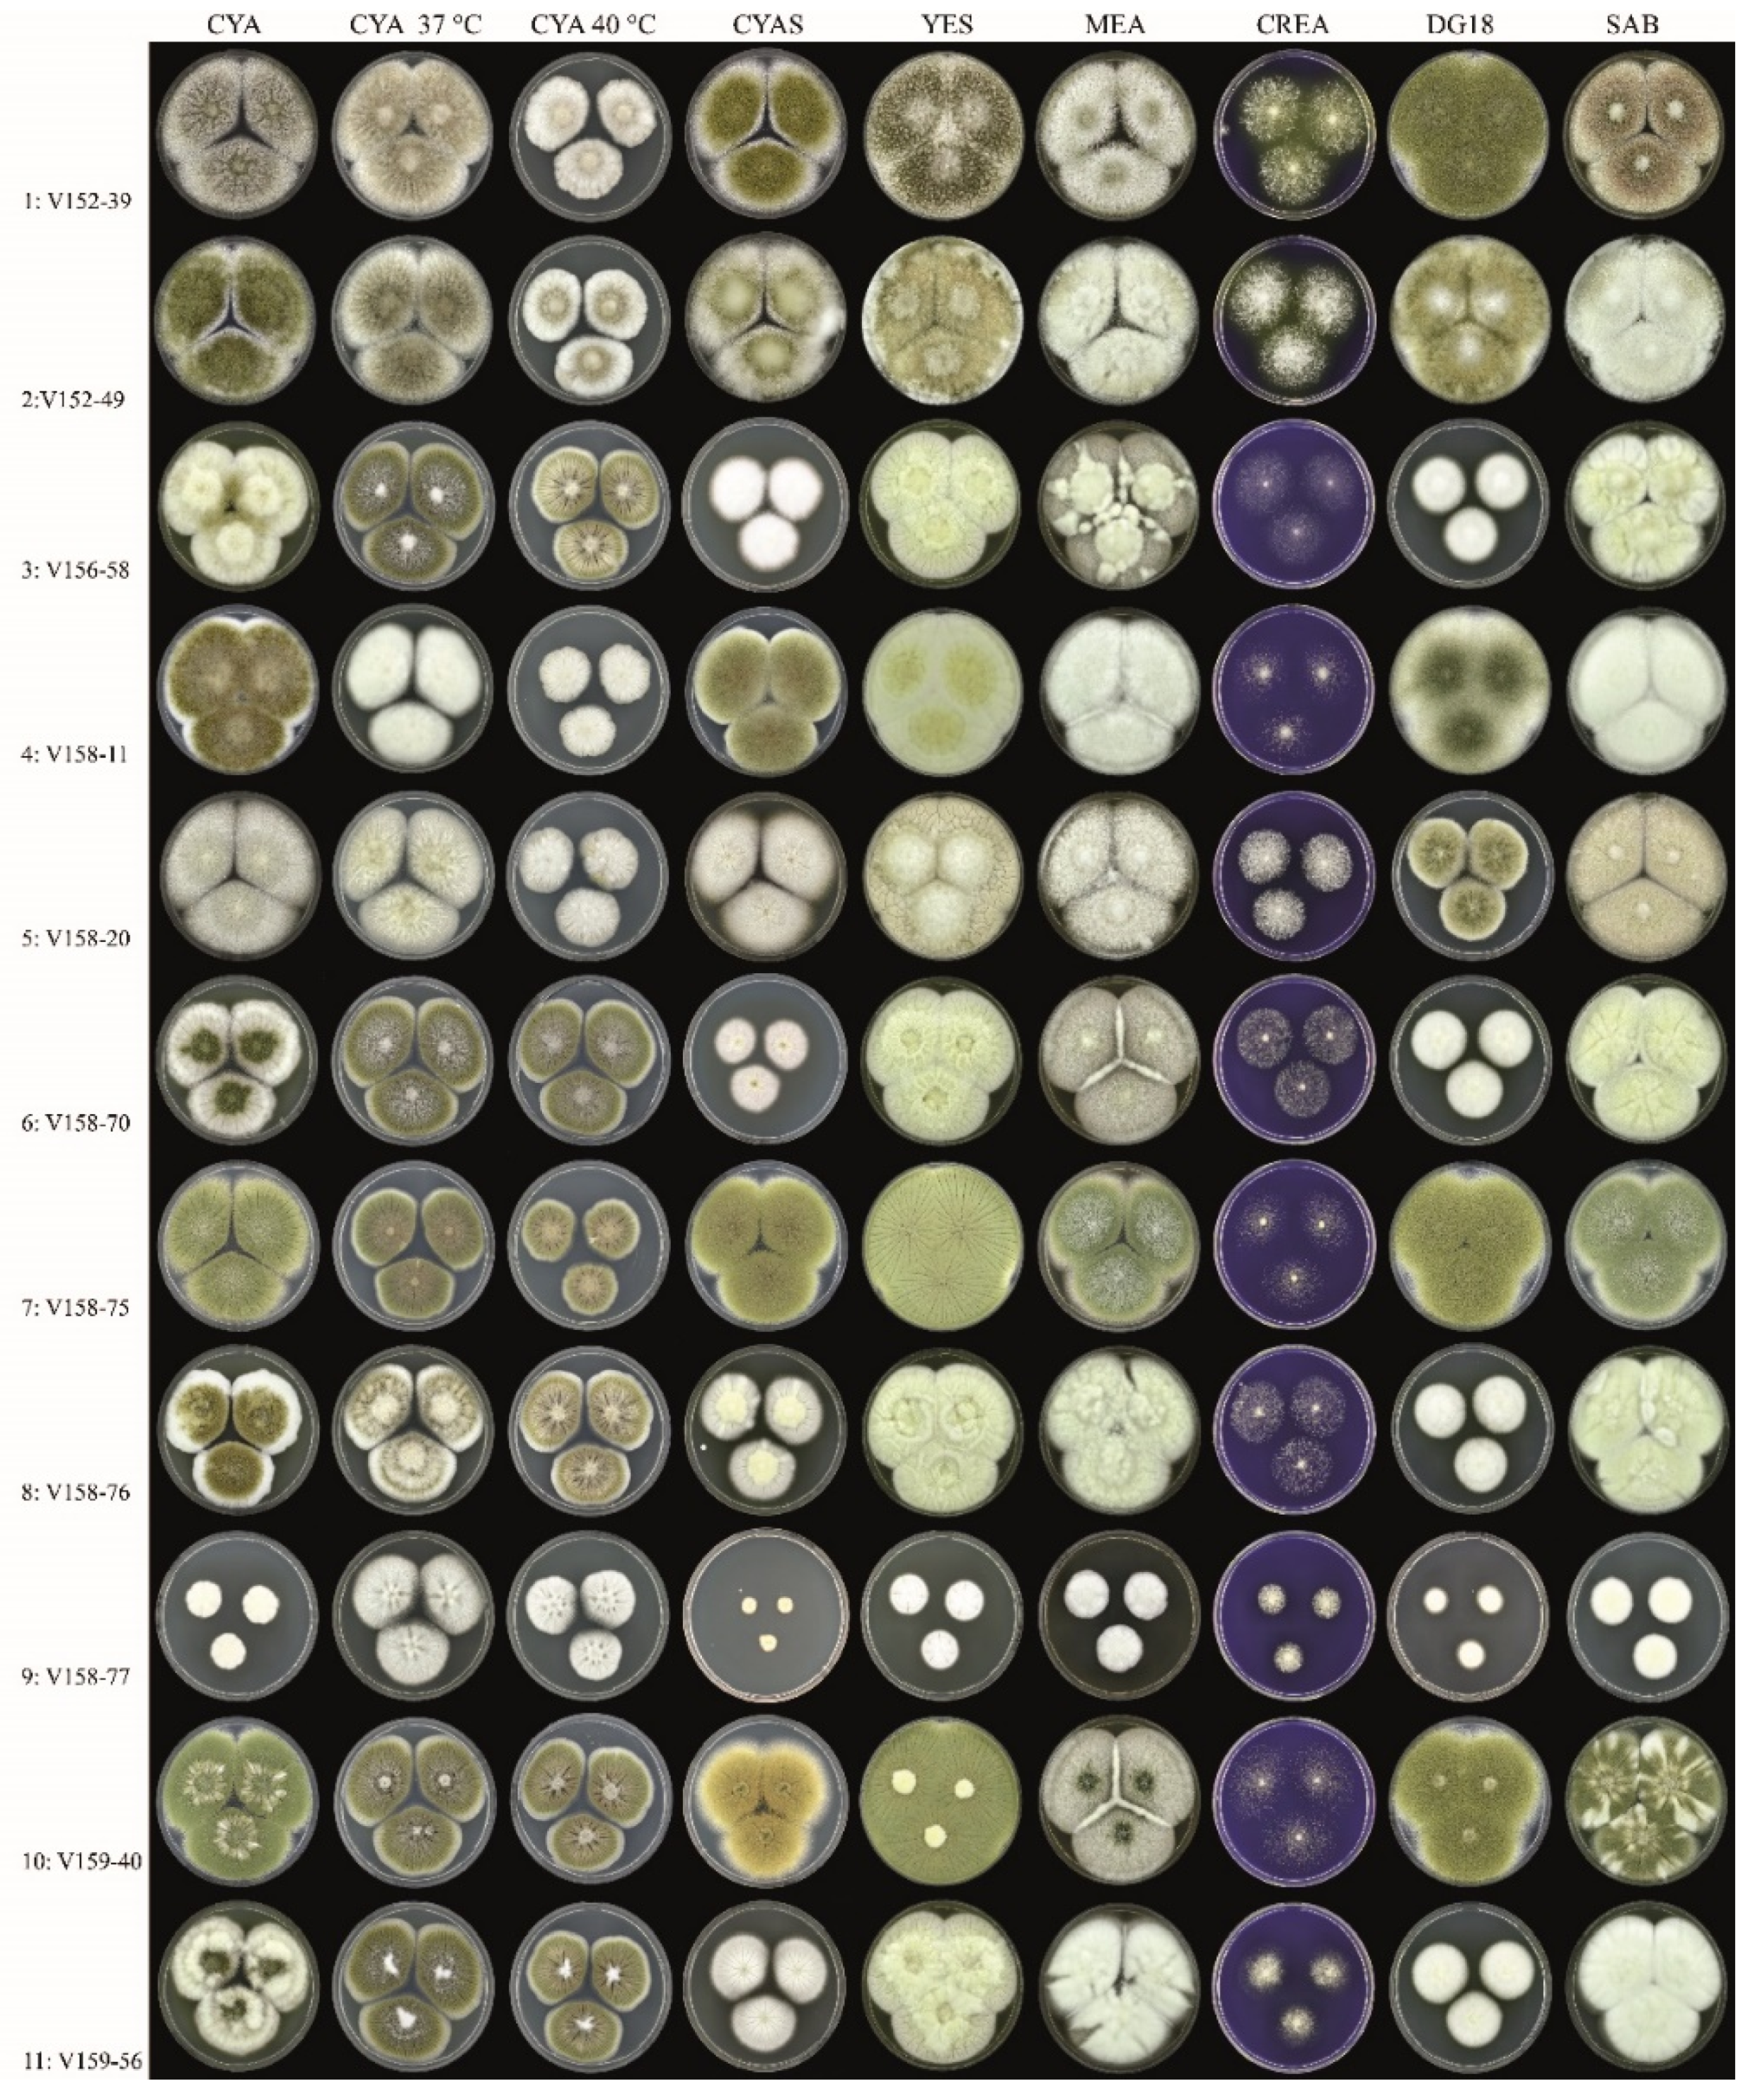

3.1. Strains, Phenotypical Analysis and Genotyping

| Isolate | Amino Acid Change | Colony Diameter (mm, after 7 d, 25 °C) | Unique Macromorphological Characters Compared to Isolates 1–2 a | ||||||||||||||

|---|---|---|---|---|---|---|---|---|---|---|---|---|---|---|---|---|---|

| I997N | R52G | A221T | V99A | H25Q | P38L | A561T | Y119F | K1757R | I570T | T159I | R669Q | E35* | P445L | CYAS | DG18 | ||

| 3 | x | x | x | x | x | x | x | x | x | x | 36–38 | 32–34 | Colony diameters smaller on DG18 and CYAS, sporulation variable | ||||

| 4 | x | x | x | x | 50–53 | >60 | Colony diameters slightly smaller on CYAS; greenish-brown-colored conidia | ||||||||||

| 5 | x | x | x | x | x | x | x | x | 54–58 | 36–38 | Colony diameters smaller on DG18, slightly smaller on CYAS; sporulation generally absent or weak | ||||||

| 6 | x | x | x | x | x | x | x | x | x | 26–30 | 32–34 | Colony diameters smaller on DG18 and CYAS; sporulation variable | |||||

| 7 | x | >60 | >60 | Colony diameters similar as Isolates 1–2; abundant sporulation on all agar media, except creatine agar | |||||||||||||

| 8 | x | x | x | x | x | x | x | x | x | 36–38 | 29–32 | Colony diameters smaller on DG18 and CYAS; sporulation variable | |||||

| 9 | x | x | x | x | x | x | 8–10 | 16–18 | Colony diameters restricted on all agar media; sporulation absent | ||||||||

| 10 | x | 54–58 | >60 | Growth diameters slightly smaller on CYAS, sporulation generally moderate or good | |||||||||||||

| 11 | x | x | x | x | x | x | x | x | 35–38 | 30–33 | Colony diameters smaller on DG18 and CYAS; sporulation variable | ||||||